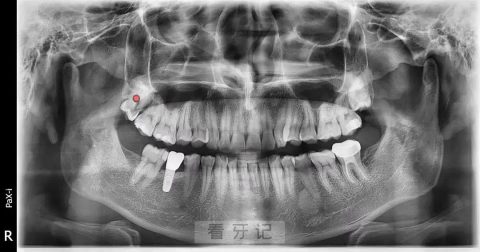

(2)全景片

包括全景曲面断层片、头颅侧位片,以二维影像的形式展现口腔的整体情况及正畸所需测量。可以了解牙齿整体情况。

不仅了解牙齿本身病变情况,还了解牙根下是否有囊肿、周围骨头是否吸收、牙槽骨内是否有埋伏牙、多生牙等。